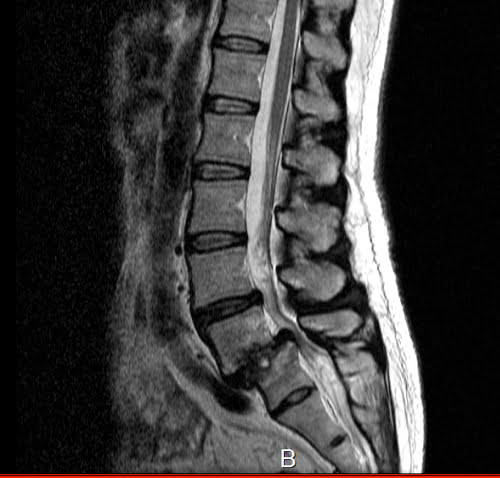

うちの他のお客様の画像データですが

すべり症はこんな感じで骨がずれてしまっています。

ですが、今までの経験上、これだけのズレがあって痛みや痺れがあっても

施術を続けていくうちに徐々に痛みや痺れが消えていく方が殆どです。

ですので先程の分離症があっても日常生活に支障がない場合が大部分

ということも踏まえて、脊椎分離すべり症と腰の痛みは

直接関係ない場合が多い。

そう考えてもいいのではないでしょうか?